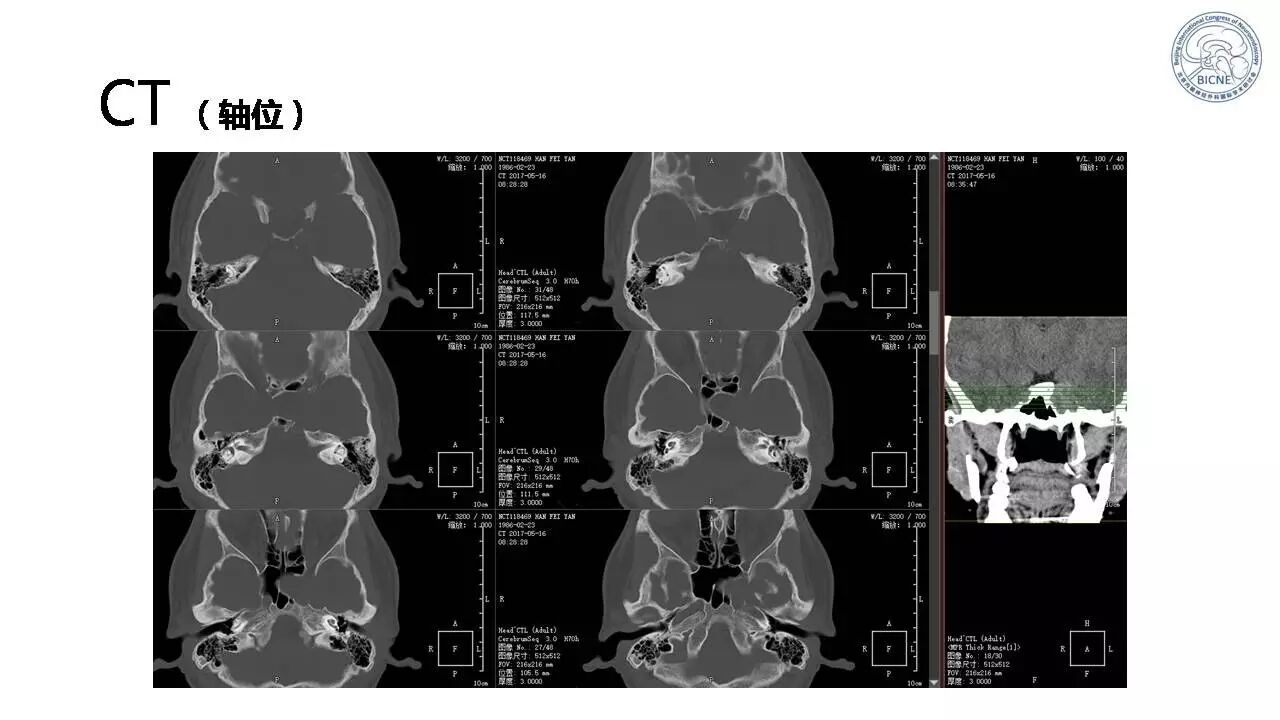

(一)张亚卓教授:脊索瘤经鼻内镜下治疗

![]()